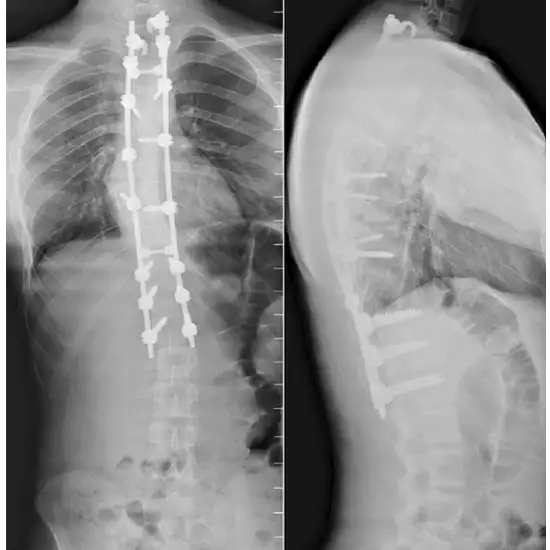

The X-Ray Whole Spine AP LAT View exam captures the spine's natural bone structure and soft tissues. It finds fractures, herniated discs, arthritis, spondylosis, and tumors. The patient stands or lies down. X-ray rays scan the spine's inside. For AP (anteroposterior) and LAT (lateral) views, the X-ray beam is placed in front of and sideways to the patient's body.

• To examine for anomalies in the spine's curvature, such as lordosis, kyphosis, scoliosis, or birth deformities.